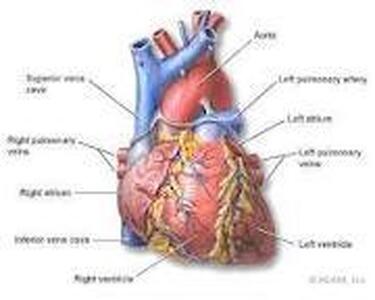

۱۴۰۳/۰۱/۲۲ / سایت سلامت نیوز / سلامت